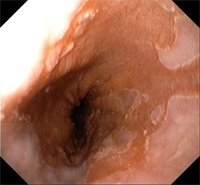

El esófago de Barrett es una alteración de la mucosa de esófago que, como consecuencia del reflujo gastroesofágico persistente, se inflama tanto que incluso llega a cambiar de características histológicas. Este cambio de tejido es la única característica que nos permitirá hacer el diagnóstico, es decir, el diagnóstico de esófago de Barrett no se puede establecer por el aspecto de la mucosa en la endoscopia ni por los síntomas del paciente ni por la demostración de un exceso de ácido refluido. Lo único que nos da el diagnóstico es demostrar que en el esófago se encuentra tejido de tipo intestinal (lo que se conoce como metaplasia intestinal) y si no hay tejido de estas características no se puede hacer el diagnóstico de esófago de Barrett.

La alteración de la mucosa que se observa en estos pacientes necesita ser controlada periódicamente porque en muy pocos casos la inflamación puede provocar degeneración del tejido y es necesario detectarlo de forma precoz para poder tratarlo.